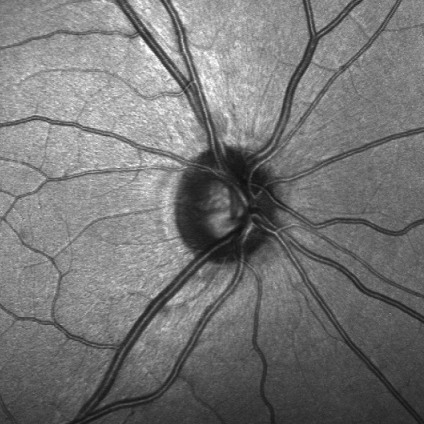

Imagen del nervio óptico registrada con un tomógrafo de coherencia óptica

El glaucoma es una enfermedad ocular que se caracteriza por la pérdida de visión como consecuencia de un daño irreversible en el nervio óptico, provocada generalmente por un aumento de la presión intraocular.

La prevalencia del glaucoma crónico es del 3% en la población general, lo que supone que en España hay por encima del millón de personas que sufren la enfermedad. Se calcula que un 50% de los pacientes con glaucoma permanecen no diagnosticados hasta etapas avanzadas de la enfermedad. De aquí parte la necesidad de implementar nuevas técnicas de diagnóstico precoz en glaucoma para disminuir y atenuar la pérdida visual que esta enfermedad produce en nuestros pacientes. En este sentido va dirigido el aspecto asistencial de este acuerdo.